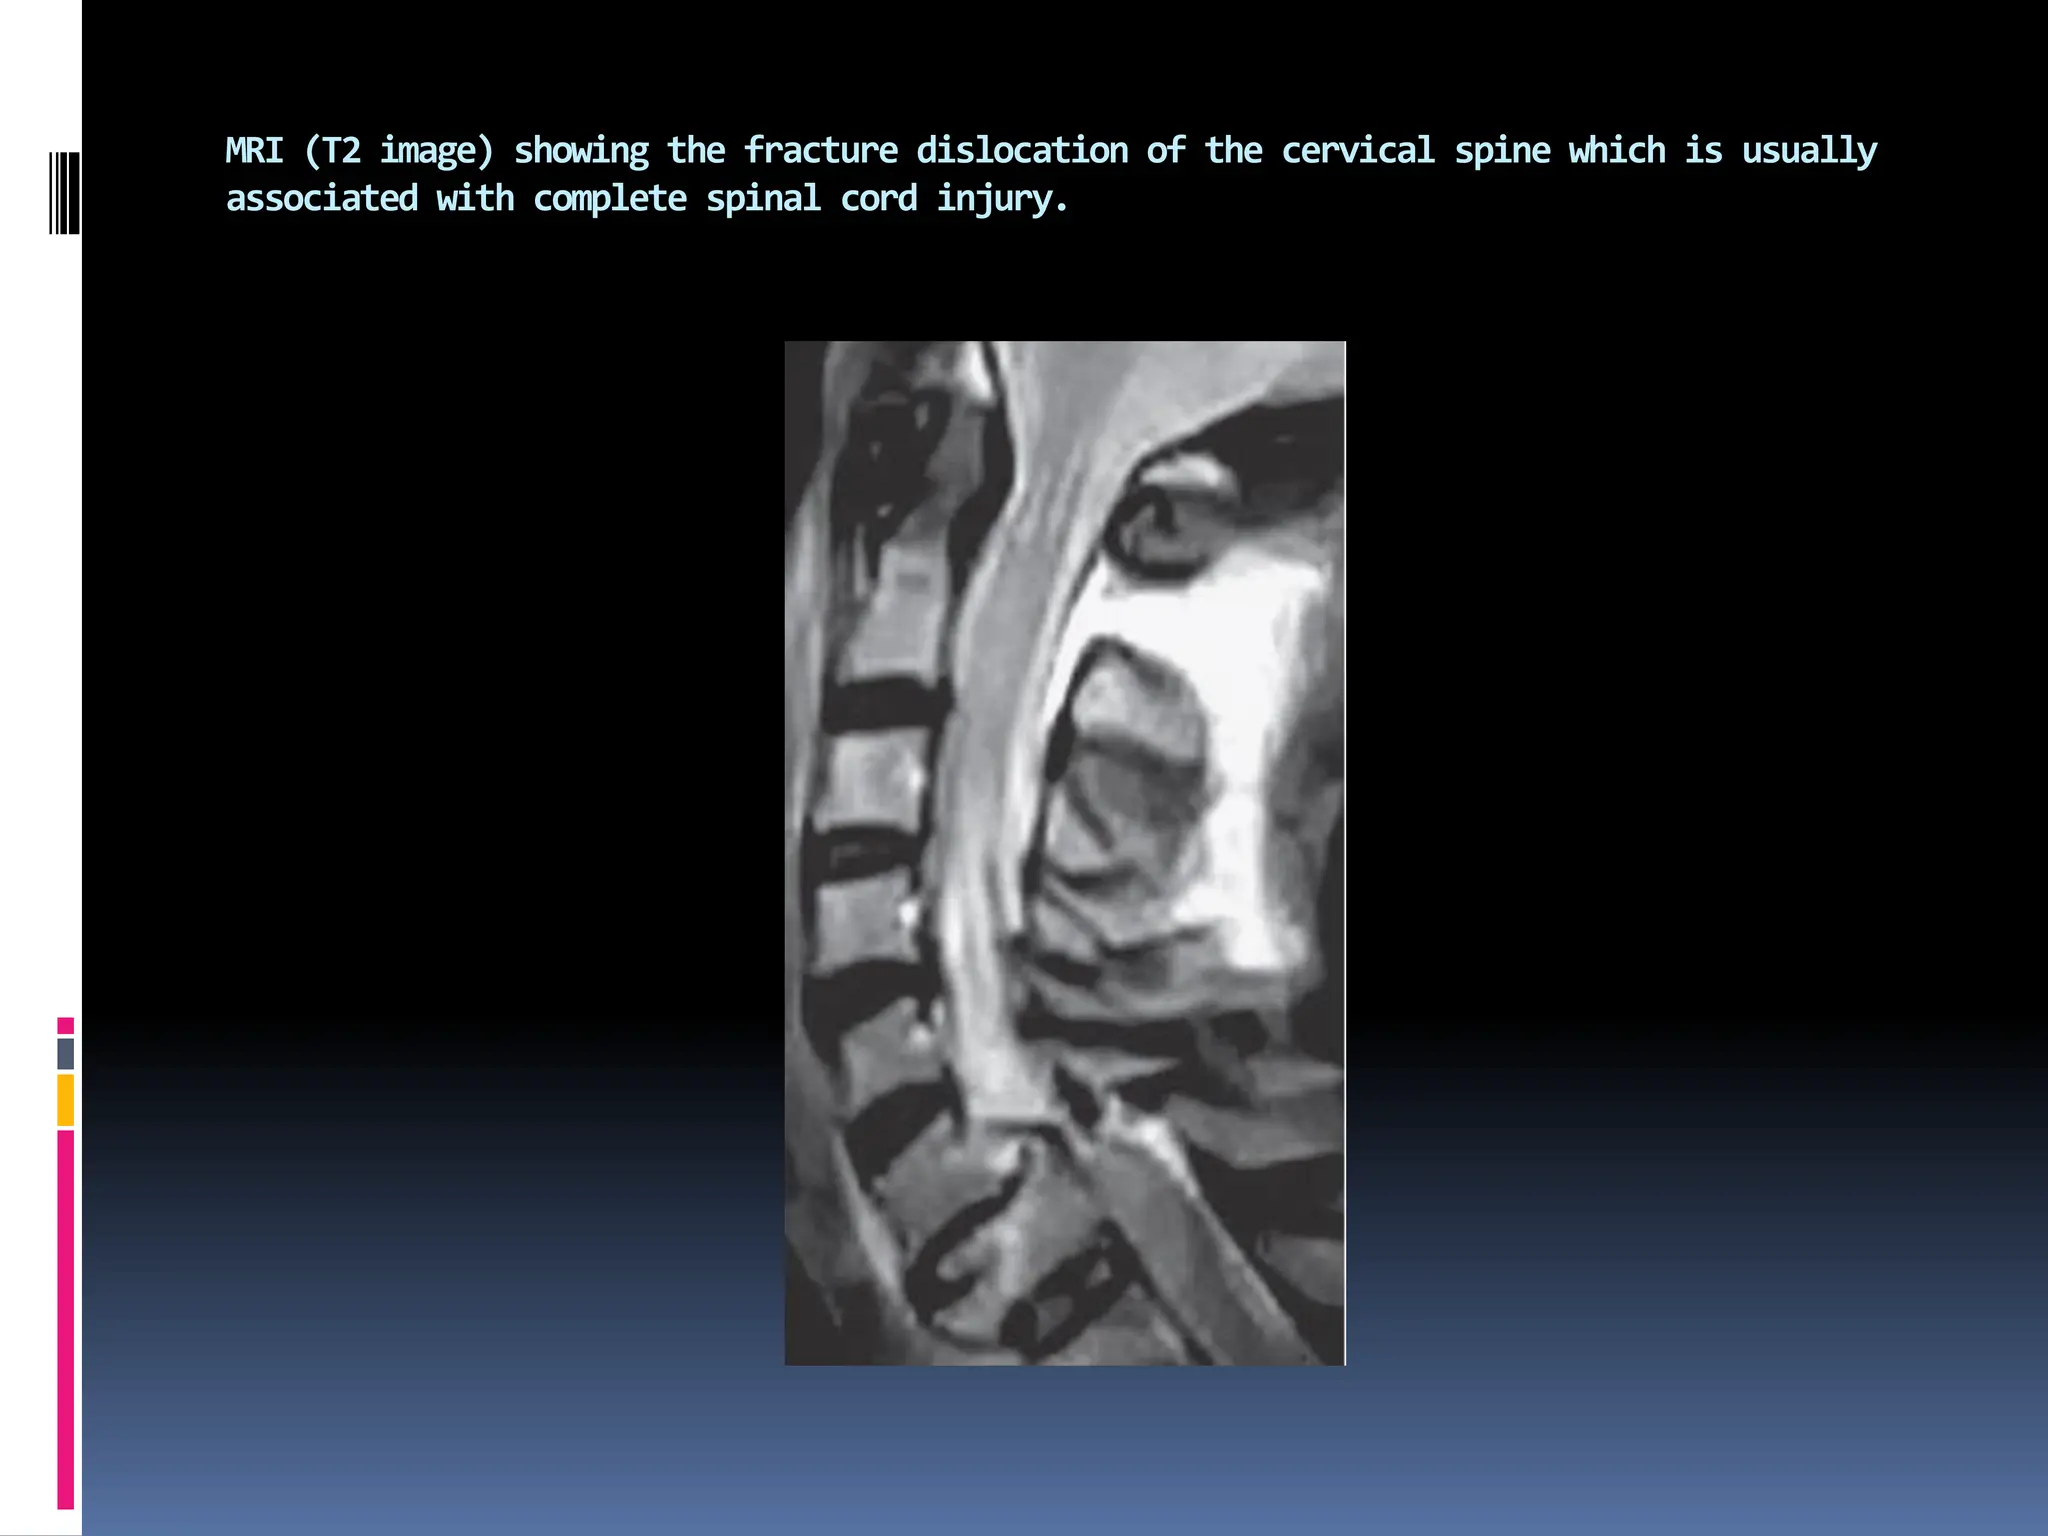

MRI (T2 image) showing the fracture dislocation of the cervical spine which is usually

associated with complete spinal cord injury.